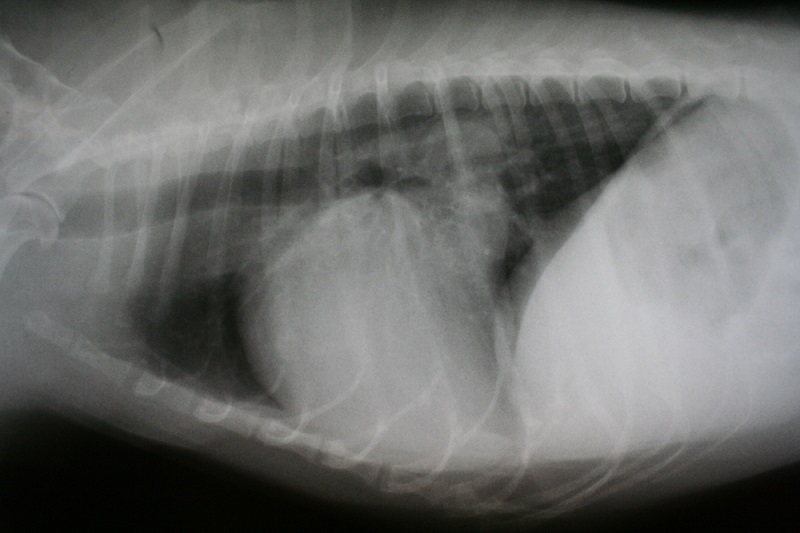

Advanced Digital X-rays

At Petdoc Urgent Care in Willow Grove, PA , we are proud to be on the cutting edge of medical technology. Radiology is a technique and diagnostic tool that we use to look inside the body in an entirely non-invasive way. X-rays allow us to create images of all the body’s organs.

In other words, the use of radiology gives us a view of the internal organs in your pets’ body that we otherwise could not see. It is a valuable diagnostic tool that helps veterinarians detect and prevent illness.